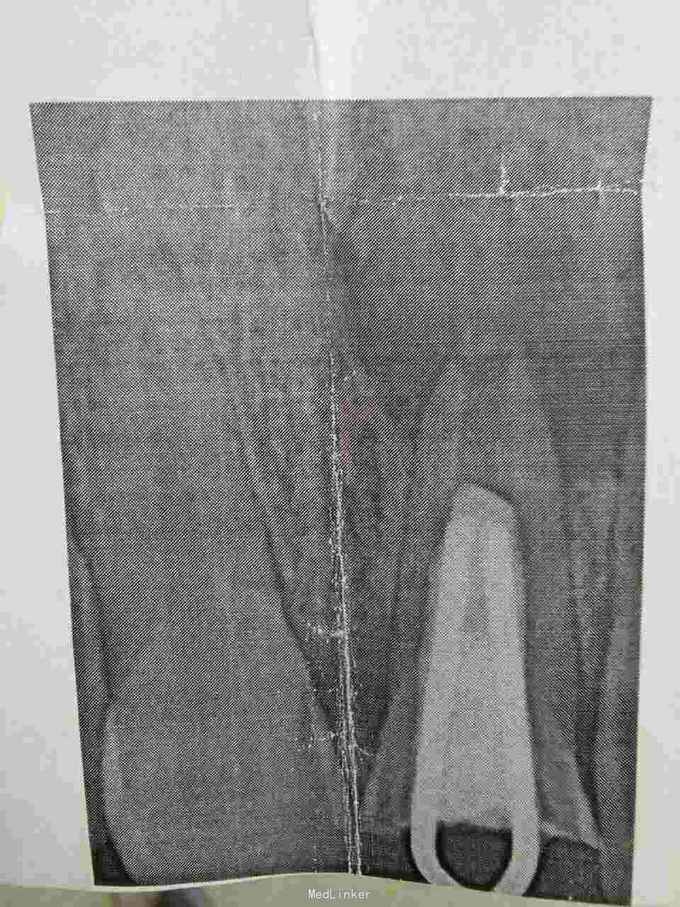

患者,男,22岁。已在外院就诊检查,要求在本院医疗。 8岁时外伤门牙冠折,今年牙龈总是化脓肿胀。

根尖囊肿